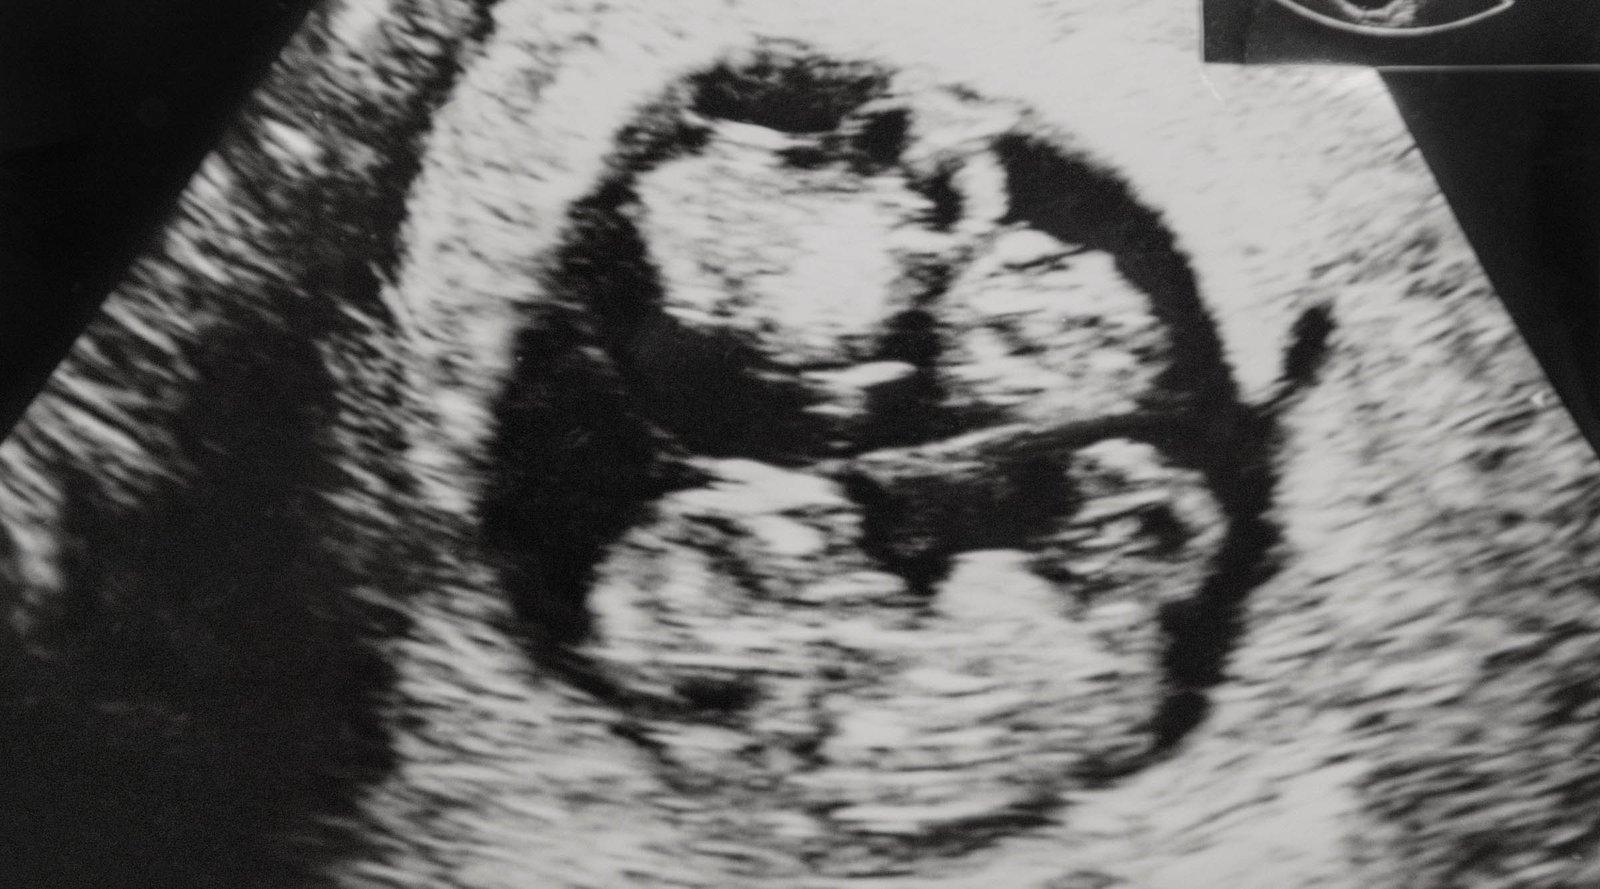

Artigos, Dicas e Novidades sobre Ginecologia, Cardiologia, Mastologia e Obstetria